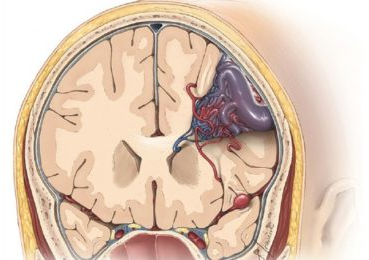

Brain arteriovenous malformations, or AVMs, are abnormal clusters of blood vessels within the brain. They are thought to arise during brain development in utero or shortly after birth. In these malformations, there are unusual connections between arteries and veins, which over time can weaken and possibly rupture.

Figure 1. Brain AVM

An AVM is a collection of abnormal vessels with higher than usual blood flow, which over years can weaken and potentially rupture. If an AVM ruptures, blood escapes the vessels into the brain. Symptoms of a bleed may include body weakness, loss of speech, numbness, paralysis, coma, and even death. People with unruptured AVMs have an approximately two percent chance of the AVM bleeding each year. The goal of AVM treatment is to cure the AVM and prevent future brain bleeds. Each AVM is unique and management should be carefully discussed with a cerebrovascular professional.